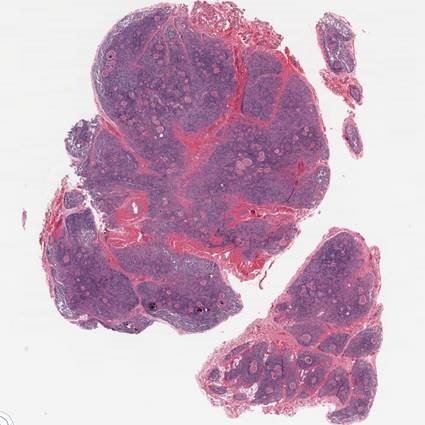

This protocol will detail our method of utilizing the H&E stain as a nonspecific entity to achieve optimal results in our staining process for our research samples.

Hematoxylin and Eosin stains are used in many areas of the laboratory, including frozen sections, fine needle aspirates, and paraffin fixed embedded tissues. There are multiple factors involved in determining what makes a well stained slide, and one of the primary factors involved in the final product is pathologist preference. Other important factors also play important roles in your final stain, such as reagents and their quality, consistency, initial microtomy quality and selecting a sound procedure.

Hematoxylin is used to illustrate nuclear detail in cells. The resulting intensity and shade of the dye in the cells is primarily reliant on the length of time the sample spends in hematoxylin. The cytoplasmic component of the section is brought out by Eosin, which is the most commonly used counterstain in histology. It's varying shades of pink and red provide an exceptional contrast between the nuclear and cytoplasmic areas of interest.

Example of a H&E stain line.